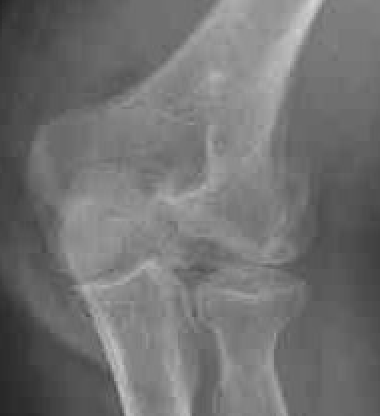

Capitellum fracture with radial head fracture